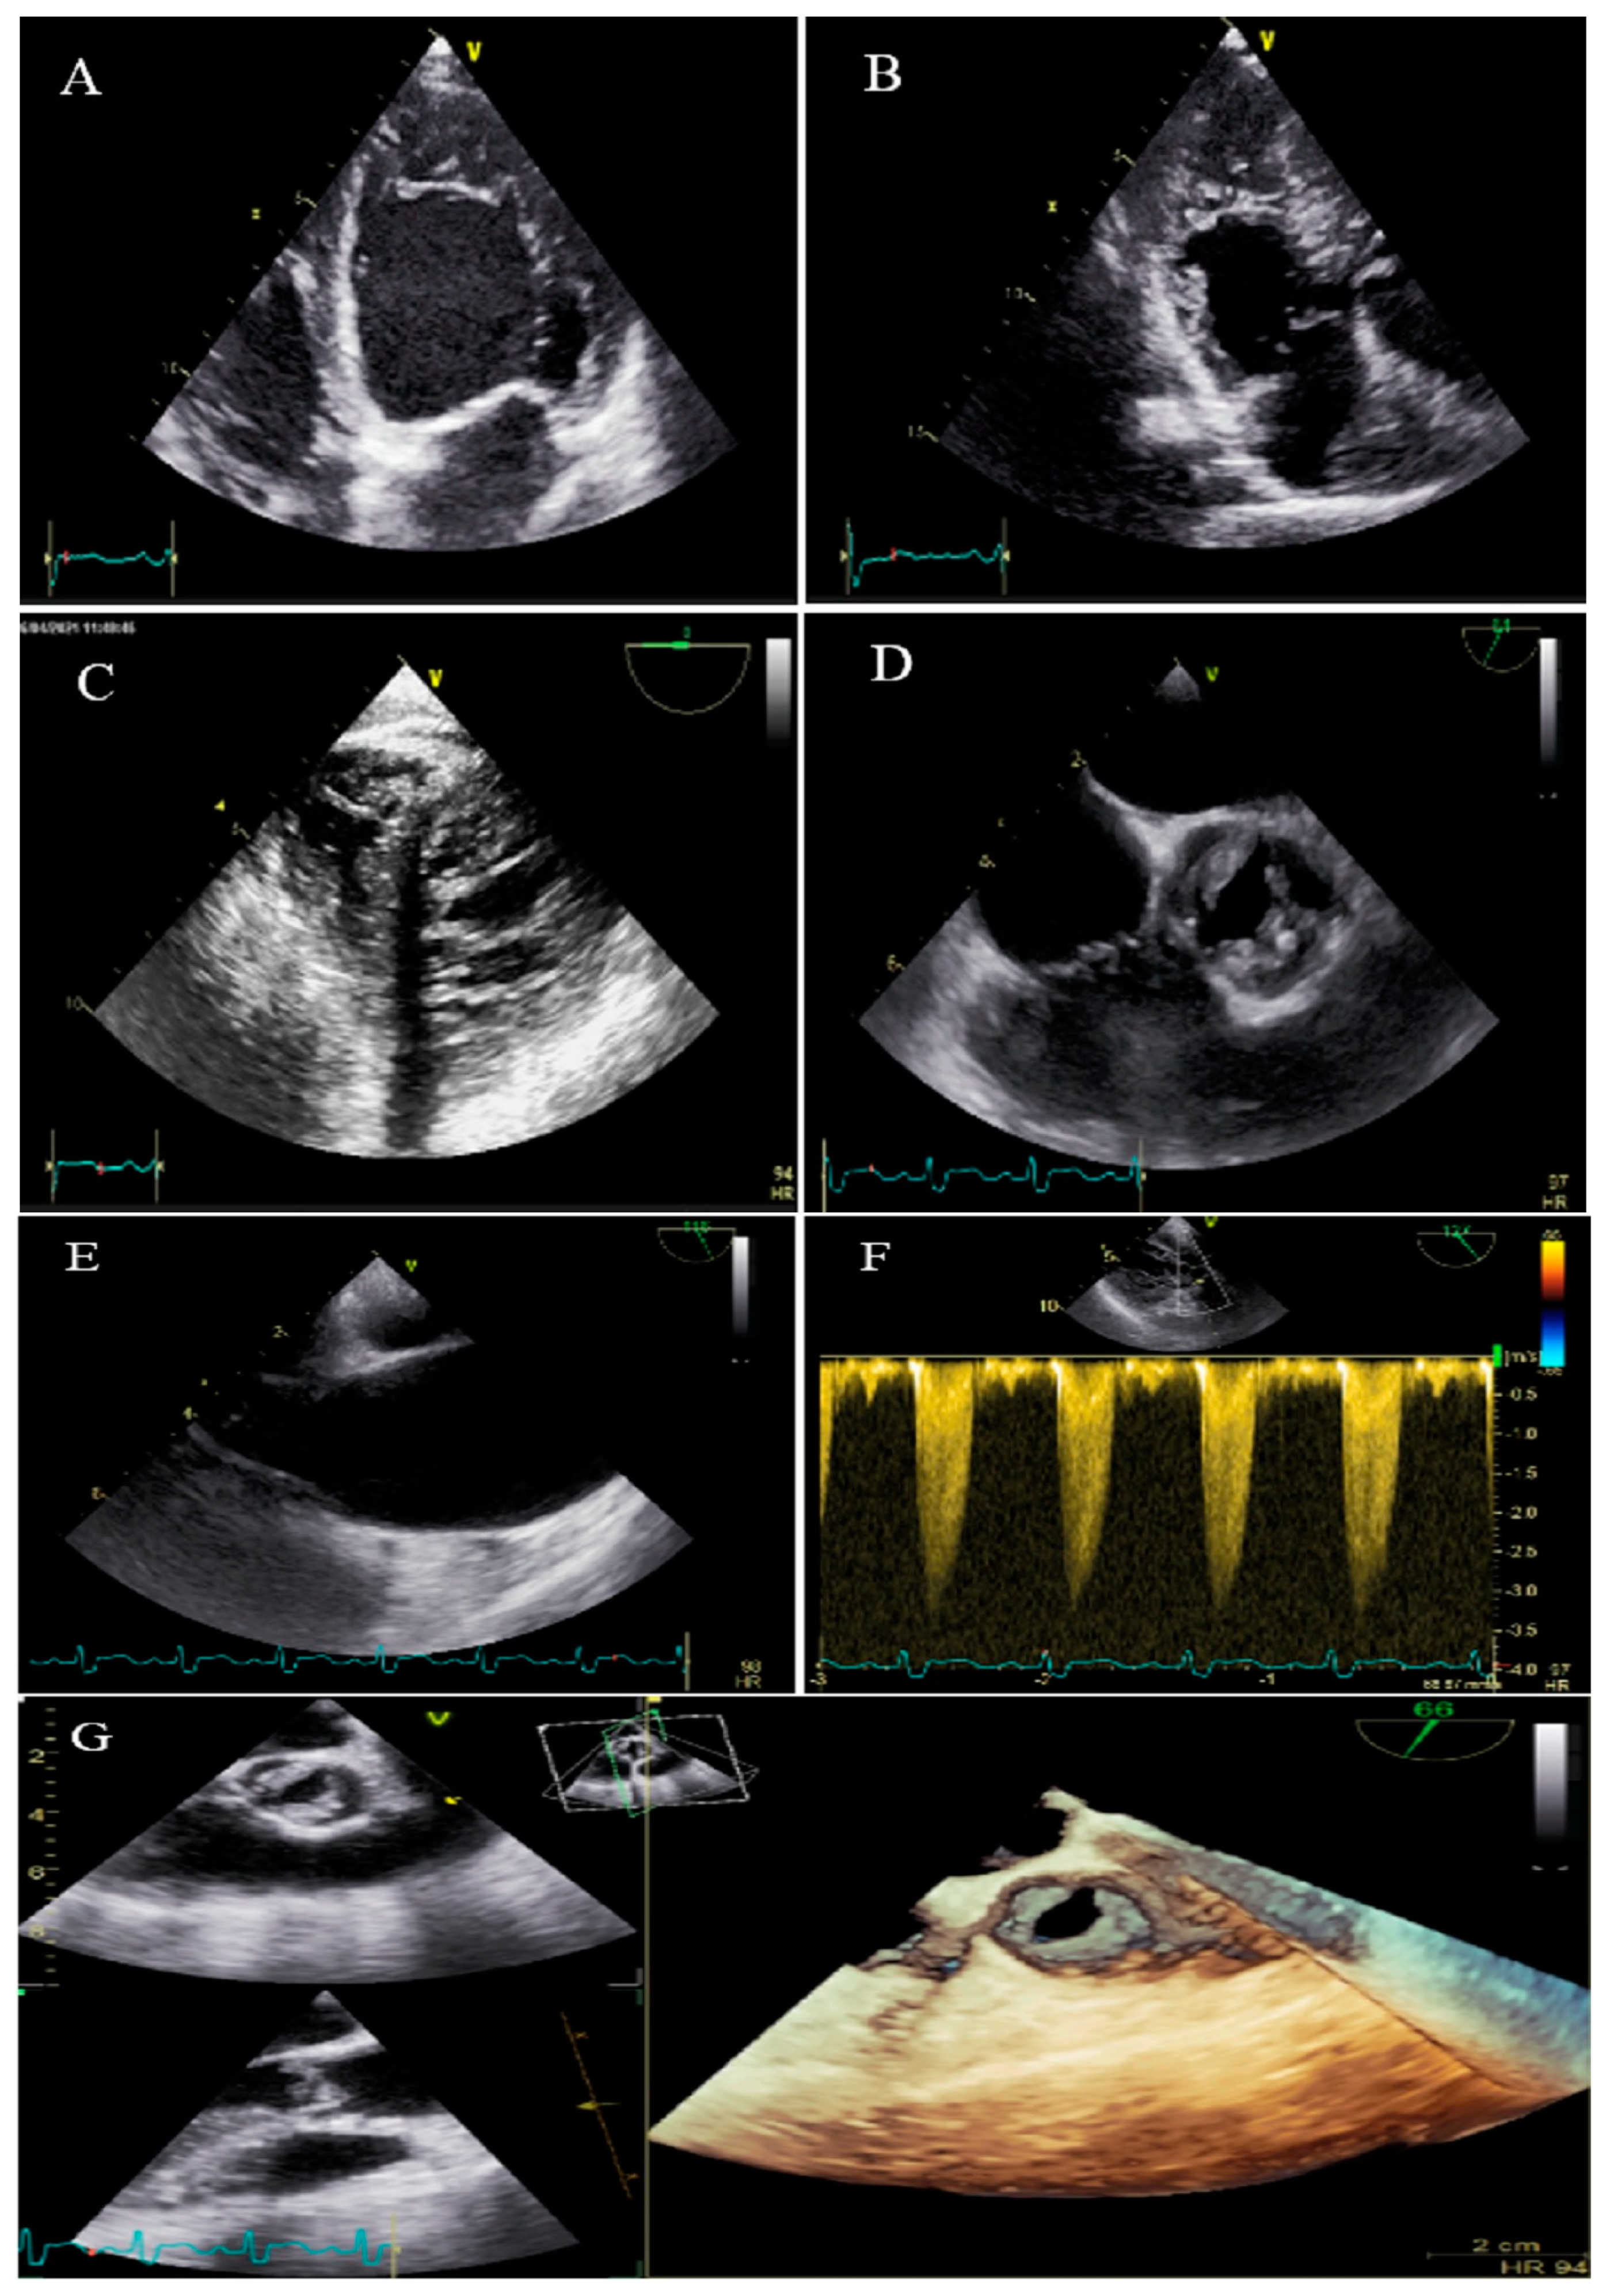

2.7. Case #7. BVNC, BAV, AS, and Dilated Aorta Ascending Aorta

A 48-year-old gentleman, a medical staffer, was referred to our clinic with dyspnea on moderate exercise and easy fatigability for 6 months, which had become worse over time. On cardiac auscultation, left- and right-sided S4 and S3 gallops, in addition to ejection systolic murmur grade III/VI in the aortic area, were audible. TTE showed non-compaction left and right ventricles with preserved biventricular systolic function, BAV, moderate AS, and dilated ascending aorta (diameter = 47 mm; indexed = 25 mm). At his request, he underwent diagnostic coronary angiography and left/right ventricular cineangiography, and the results showed patent epicardial coronaries plus hypertrabeculation of both ventricles in the biventricular cineangiography (Figure 7). A genetic study showed mutations in the MYH7 and MYBPC3 genes. The patient and the family members refused the genetic study because of the high costs of the test (not covered by the insurance). He denied undergoing CMR, due to claustrophobia, and was followed up medically (daily spironolactone 25 mg and carvedilol 6.25 mg twice per day). He was off pills 2 months later and did not return for further follow-up.

Figure 7.

Two-dimensional transthoracic echocardiographic views of case #7. (A,B); Biventricular non-compaction in apical four and three-chamber views. (C–F); Transesophageal echocardiography views, illustrating biventricular non-compaction in apical regions in addition to a thick, bicuspid aortic valve with restricted cusps motion (C,D), dilated ascending aorta (E), and increased transvalvular gradient in deep gastric view with a peak velocity of 3 m/s, in favor of moderate aortic stenosis (F). (G); Full volume three-dimensional transthoracic echocardiography, showing bicuspid, thick, and stenotic aortic valve (AVA by MPR = 1.4 cm2).